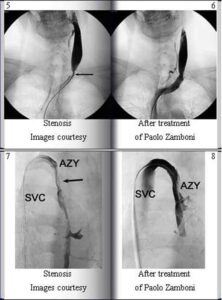

Il prof. Zamboni, i Suoi studi sulla circolazione cerebrale ridotta a niente in una percentuale non trascurabile di malati di...